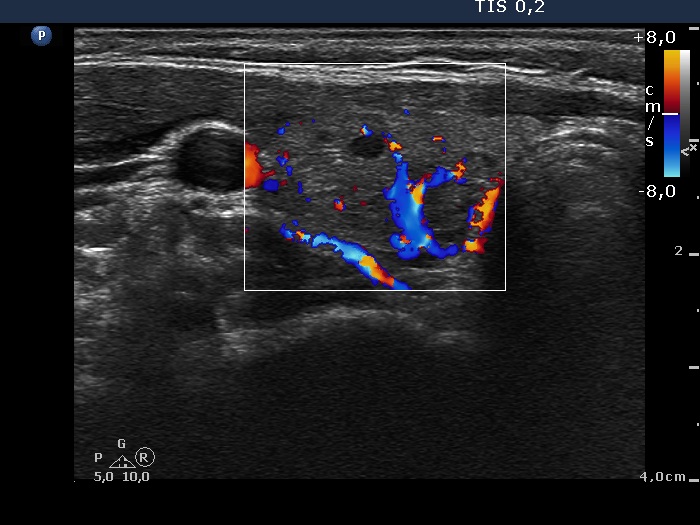

Ultrasonography. The thyroid was echonormal. There were multiple moderately hypoechogenic lesions in the right lobe. The palpable nodule was echonormal and presented halo sign and perinodular blood flow.